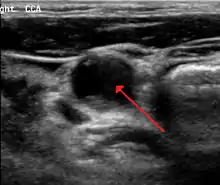

Carotid artery stenosis is usually diagnosed by color flow duplex ultrasound scan of the carotid arteries in the neck. This involves no radiation, no needles and no contrast agents that may cause allergic reactions. This test has good sensitivity and specificity.[16]

Typically duplex ultrasound scan is the only investigation required for decision making in carotid stenosis as it is widely available and rapidly performed. However, further imaging can be required if the stenosis is not near the bifurcation of the carotid artery.[17]

One of several different imaging modalities, such as a computed tomography angiogram (CTA)[18][19][20] or magnetic resonance angiogram (MRA) may be useful. Each imaging modality has its advantages and disadvantages - Magnetic resonance angiography and CT angiography with contrast is contraindicated in patients with chronic kidney disease, catheter angiography has a 0.5% to 1.0% risk of stroke, MI, arterial injury or retroperitoneal bleeding. The investigation chosen will depend on the clinical question and the imaging expertise, experience and equipment available.[21]